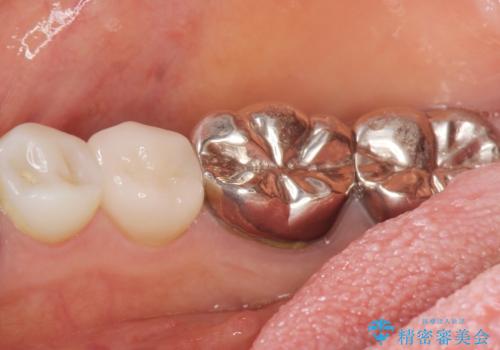

根管治療後、セラミッククラウンによる補綴治療を行いました。

根管治療により痛みがなくなり、ご安心頂けました。

セラミッククラウンの自然な仕上がりにも喜んで下さいました。

クラウンの種類:オールセラミッククラウン エコノミー